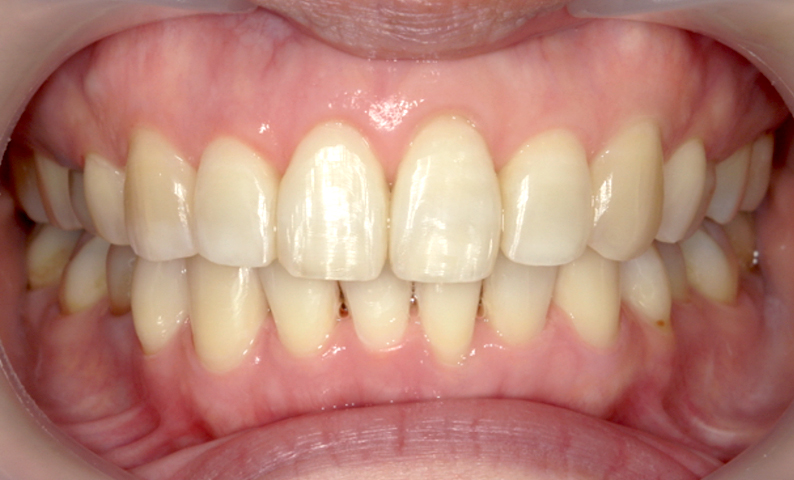

症例_002 上顎だけの部分矯正

治療期間:7ヶ月金額:30万円+税女性前歯のガタガタ上の前歯だけ

| Before | After |

|---|---|

|